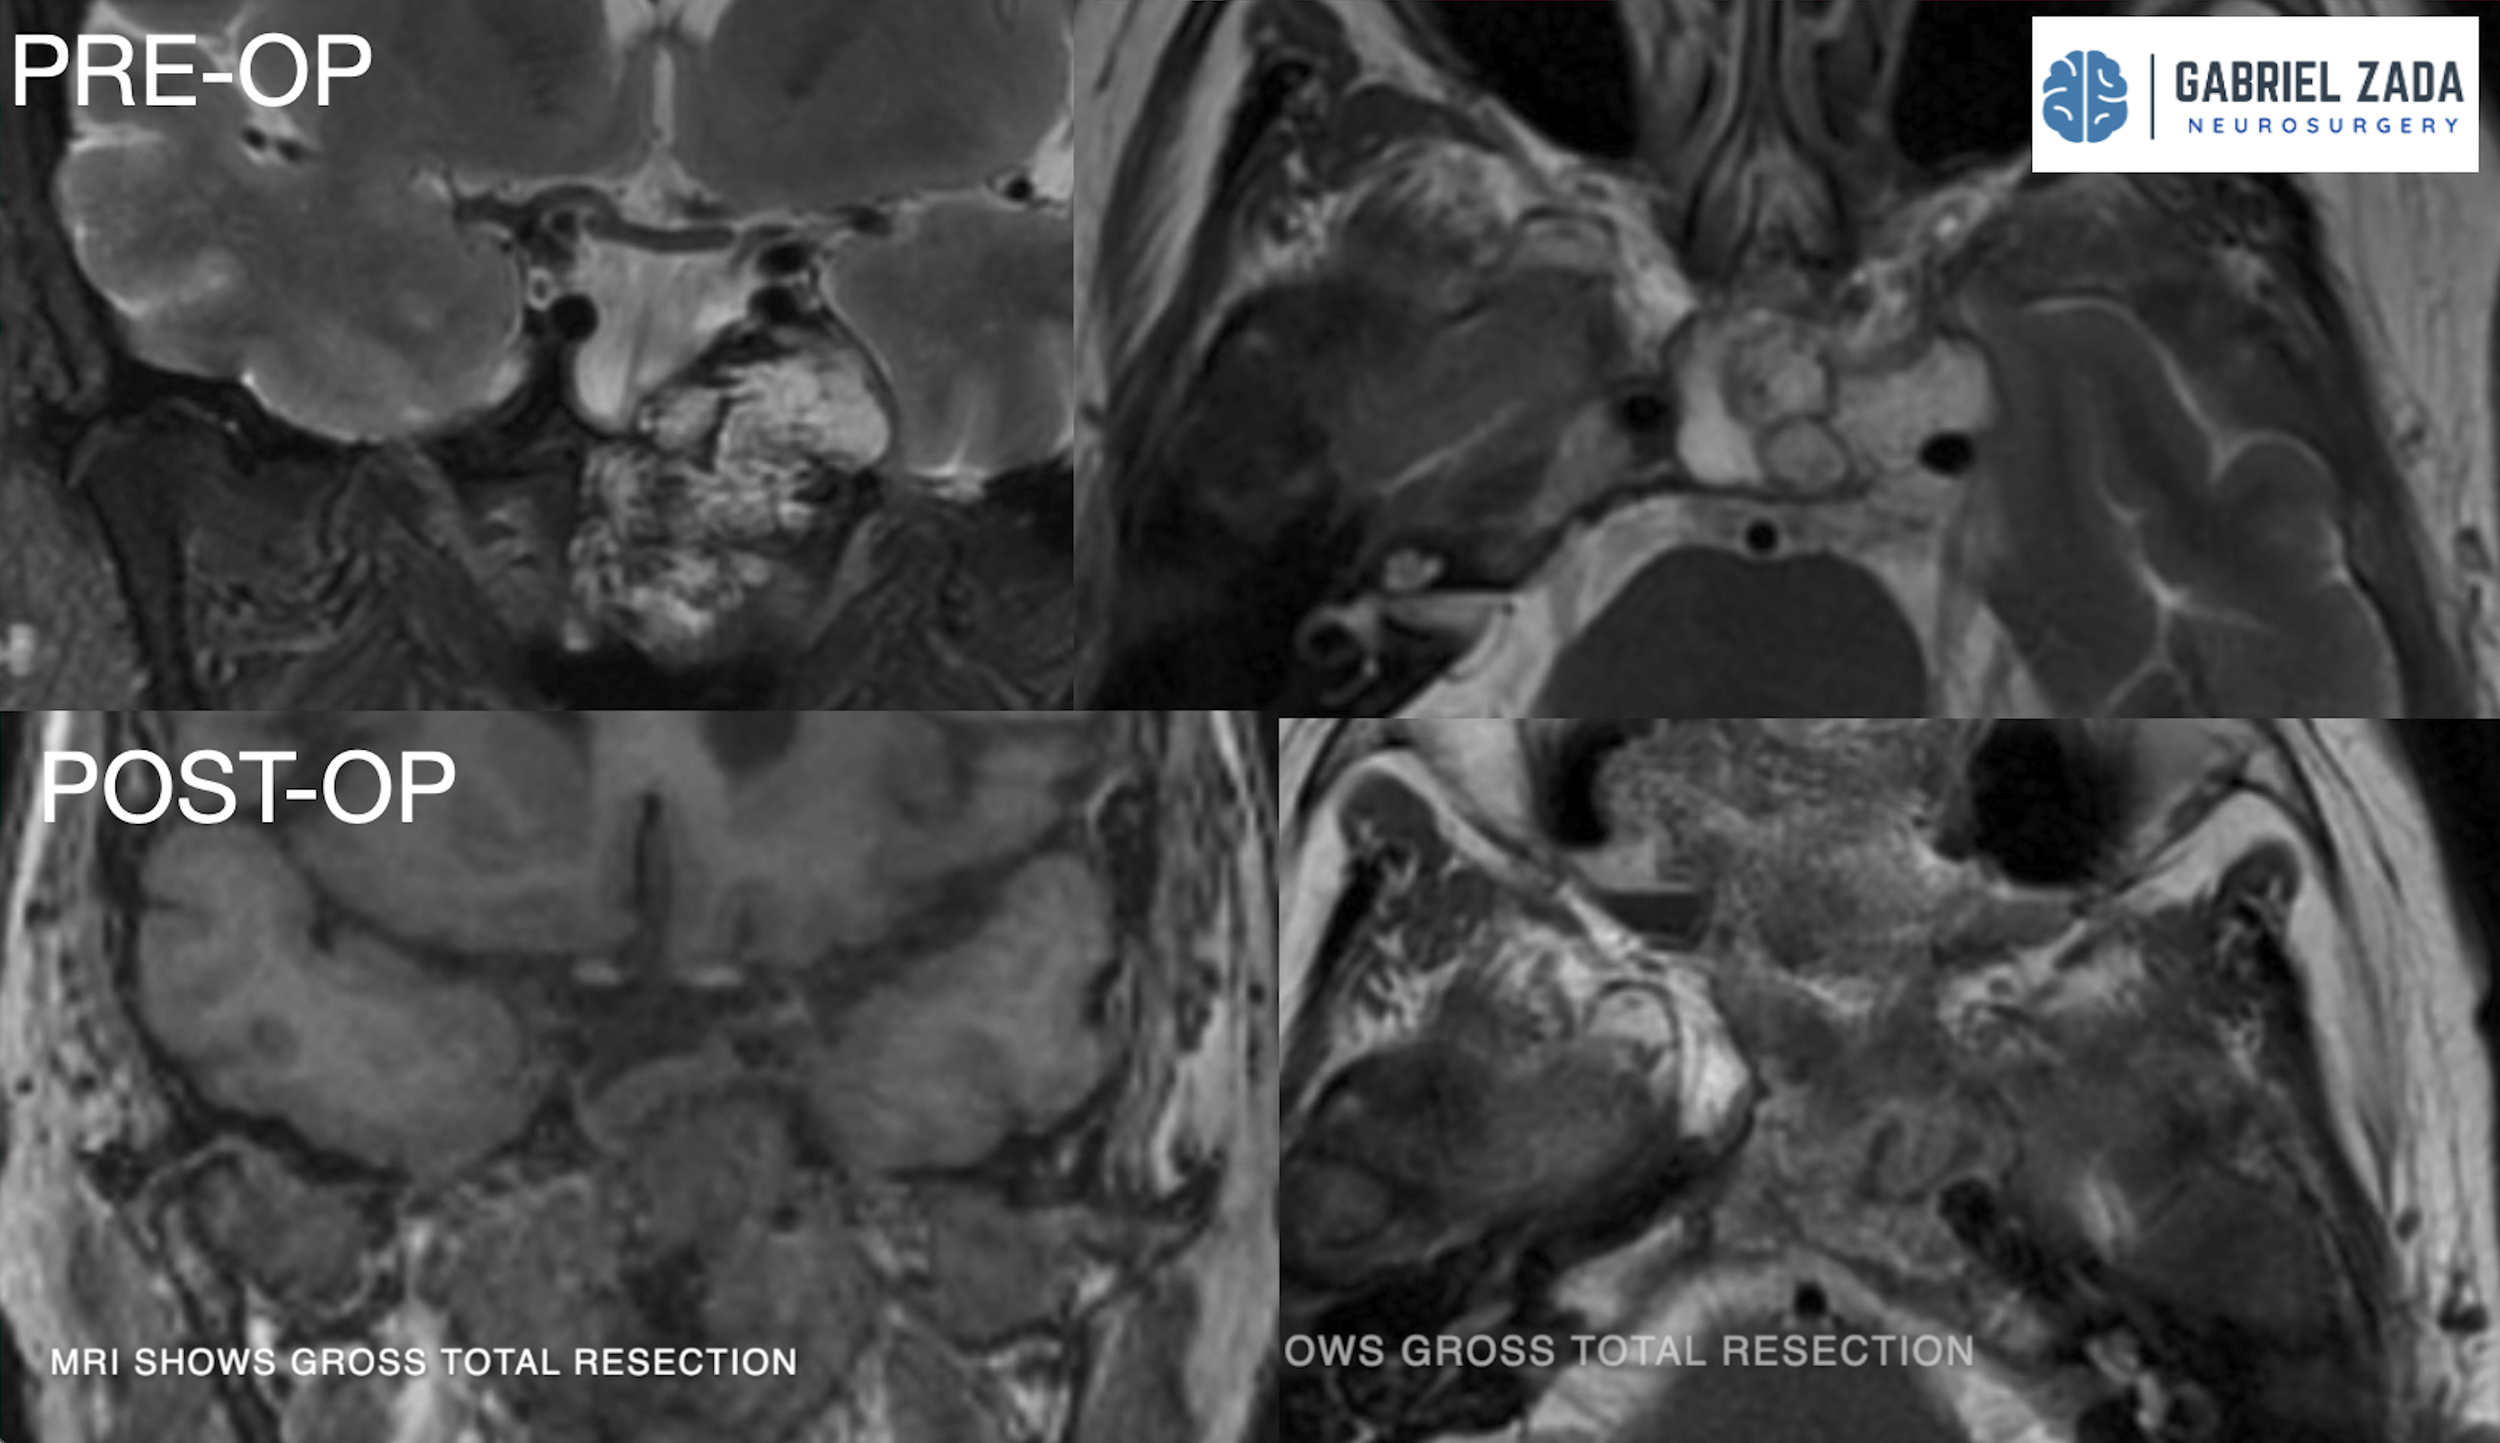

Explore this comprehensive gallery featuring pre‑ and post‑operative imaging of patients with skull‑base tumors treated by Gabriel Zada, MD, MS, FAANS, FACS. These cases highlight Dr. Zada’s expertise in advanced neurosurgical techniques and outcomes.

*Representative cases shown for educational purposes. All images de-identified. Individual results vary.